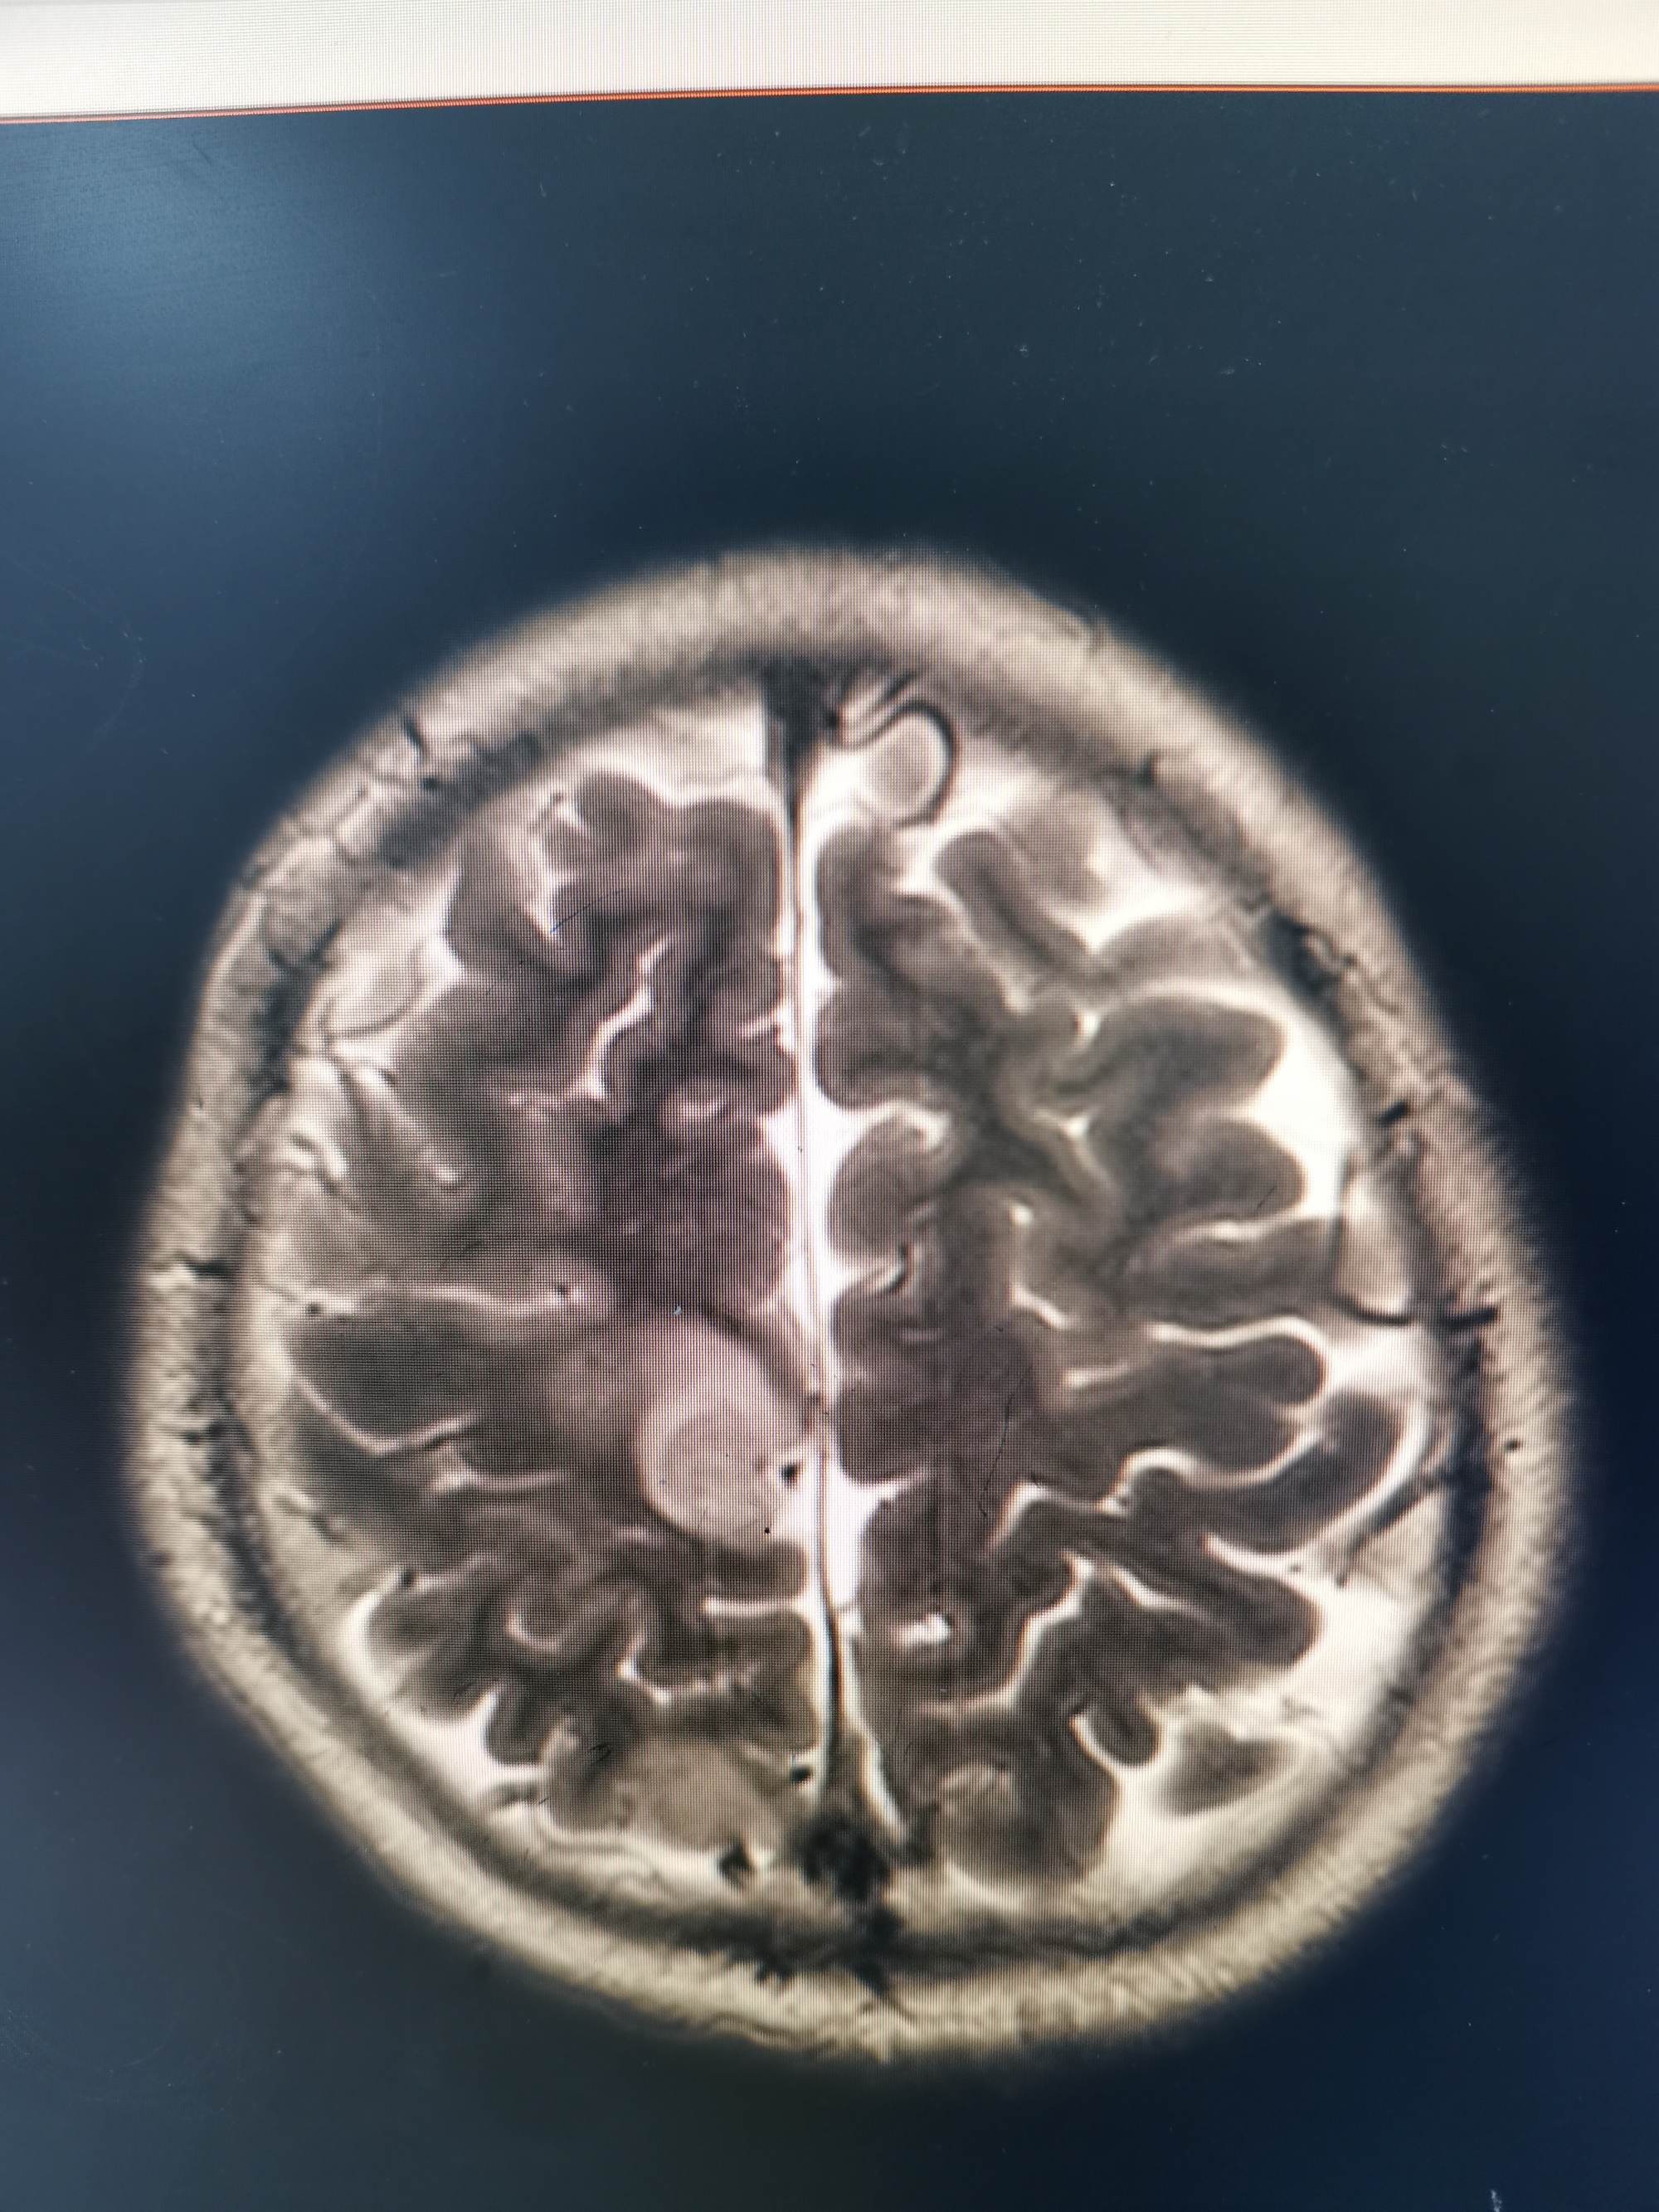

外院磁共振提示右侧顶叶病变

入院后急查头颅磁共振发现顶叶又新发两个病灶。

磁共振发现顶叶又新发两个病灶

磁敏感成像考虑首发病灶为出血。